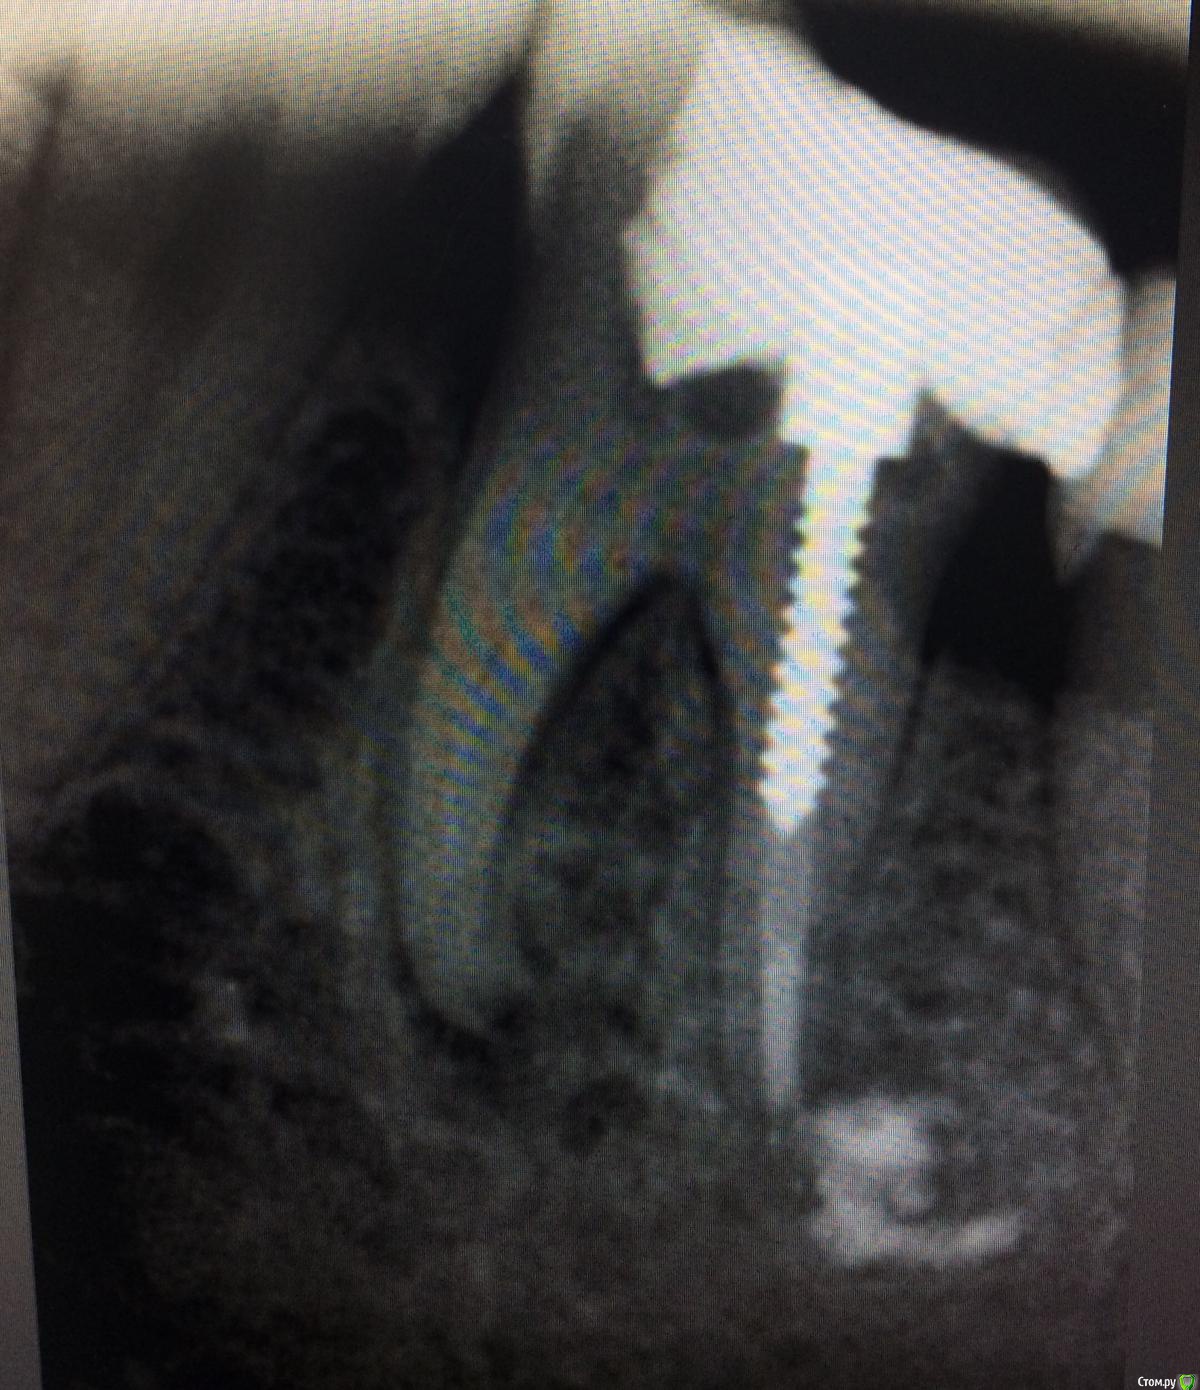

Алсушка91 Опубликовано 8 февраля, 2019 Поделиться Опубликовано 8 февраля, 2019 Под левым корнем киста может быть или нет подскажите пожалуйста? Спасибо. P.S. Белое облачко под правым корнет это вытек остаточной материал. Вот спорный вопрос возник по поводу левого корня Ссылка на комментарий

DmitrySH Опубликовано 8 февраля, 2019 Поделиться Опубликовано 8 февраля, 2019 Есть очаг воспаления и апикальная резорбция. 2 Ссылка на комментарий